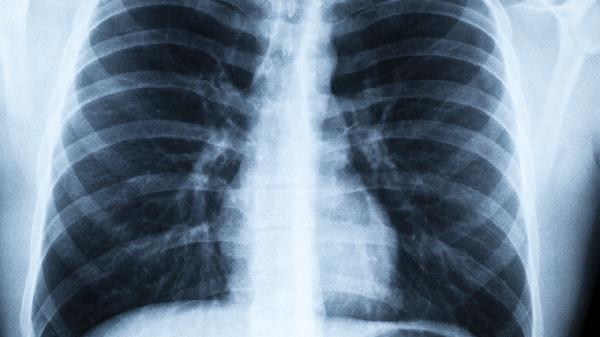

甲型和乙型流感病毒是成年人中病毒性肺炎的常见原因。病毒通过其血凝素蛋白与呼吸道上皮细胞结合,造成细胞死亡和炎症反应。患者常出现突然高烧、肌肉疼痛等全身症状,胸部CT检查可见多个肺叶呈现磨玻璃样改变。糖尿病患者和孕妇感染后容易出现急性呼吸窘迫综合征。

除了SARS-CoV-2外,像229E、OC43这样的冠状病毒也可能导致肺炎。病毒通过血管紧张素转换酶2受体进入人体细胞,病理特征是肺泡内形成透明膜。老年人常表现为淋巴细胞减少和D-二聚体升高,部分患者需要机械通气支持。